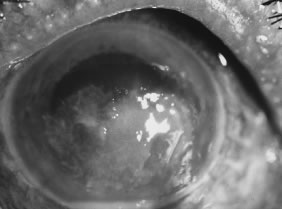

Candida infection typically produces epithelial ulceration, focal necrotizing stromal inflammation, moderate cellular infiltrate and edema in the adjacent stroma, and mild or moderate iritis in the early stages, indistinguishable from bacterial keratitis (Figs. 15, 16, and 17). Fungal elements cannot be detected by biomicroscopy. If untreated, the keratitis evolves to produce dense suppuration and necrosis of the deep stroma. Although multifocal suppuration may develop in polymicrobial keratitis, there is no distinctive sign of mixed Candida and bacterial infection (Fig. 18).

Fig. 15. C. albicans keratitis in an eye following chronic use of corticosteroid drops for herpes simplex keratitis. Note the central suppuration and perforation, endothelial plaques, and hypopyon.

Fig. 16. C. albicans following penetrating keratoplasty in a woman with severe rheumatoid arthritis. Chronic application of corticosteroid eye drop. Note the area of dense, opaque white suppuration that straddles the graft-host junction.

Fig. 17. C. albicans in a 21-year-old woman. Topical proparacaine hydrochloride abuse. Epithelial and stromal ulceration. Note the dense, white area of necrotizing stromal keratitis.